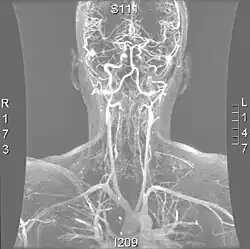

| Cerebral Angiogram obtained using an iodine based contrast medium | |

Cerebral atherosclerosis is a type of atherosclerosis where build-up of plaque in the blood vessels of the brain occurs. Some of the main components of the plaques are connective tissue, extracellular matrix, including collagen, proteoglycans, fibronectin, and elastic fibers; crystalline cholesterol, cholesteryl esters, and phospholipids; cells such as monocyte derived macrophages, T-lymphocytes, and smooth muscle cells.[1] The plaque that builds up can lead to further complications such as stroke, as the plaque disrupts blood flow within the intracranial arterioles. This causes the downstream sections of the brain that would normally be supplied by the blocked artery to suffer from ischemia.[2] Diagnosis of the disease is normally done through imaging technology such as angiograms or magnetic resonance imaging. The risk of cerebral atherosclerosis and its associated diseases appears to increase with increasing age;[3] however there are numerous factors that can be controlled in attempt to lessen risk.[4]

Due to positive remodeling the plaque build-up shown on angiogram may appear further downstream on the x-ray where the luminal diameter would look normal even though there is severe narrowing at the real site. Because angiograms require x-rays to be visualized the number of times an individual can have it done over a year is limited by the guidelines for the amount of radiation they can be exposed to in a one-year period.[2]

Magnetic resonance imaging has the ability to quantify the plaque anatomy and composition. This allows physicians to determine certain characteristics of the plaque such as how likely it is to break away from the wall and become an embolus. MRI does not use ionizing radiation, so the number of times that it is used on a single person is not a concern; however since it uses strong magnetic fields those who have metal implants cannot use this technique.[1][2]